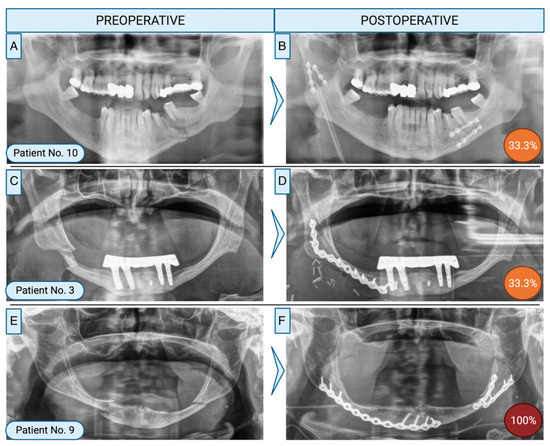

Study Design: Retrospective, descriptive observational study. Objective: The need for revision surgery after mandibular fractures is an indicator for severe postoperative complications. This study aimed to characterise this patient cohort, describe solutions to deal with complications and evaluate treatment quality as a risk [...] Read more.

Study Design: Retrospective, descriptive observational study. Objective: The need for revision surgery after mandibular fractures is an indicator for severe postoperative complications. This study aimed to characterise this patient cohort, describe solutions to deal with complications and evaluate treatment quality as a risk variable for complications. Methods: Patients with revision surgery with refixation after open reduction and internal fixation (ORIF) of a mandible fracture were included. Patient- and therapy-specific information were assessed together with postoperative complications. The quality of fixation was evaluated individually by 6 specialists. Interobserver agreement was analysed using Fleiss’ kappa. Results: Out of 630 patients, inclusion criteria were met by 17 patients (14 male, 3 female) with an average age of 43.3 (±15.5) years. Complications at the mandible body/angle/symphysis led to refixation in all cases. Main indications for refixation were osteomyelitis (52.9%) or pseudarthrosis (41.2%). Risk factors were drug-related immune suppression, local infection or substance abuse (nicotine, alcohol or drugs). Six patients did not present any of these predictors. Of these, treatment of 4 patients was rated as not in accordance to the AO principles. The interrater reliability of treatment quality assessments was 0.239. Conclusions: Patients with risk factors need to be carefully observed perioperatively after ORIF of mandibular fractures and treatments need to be adapted to these patients. Discrepancies of treatments to common guidelines may also be an independent predictor for treatment failure in patients without risk factors. Current treatment guidelines should be reevaluated concerning additional treatment strategies for patients with specific risk factors. Full article

Show Figures

Figure 1